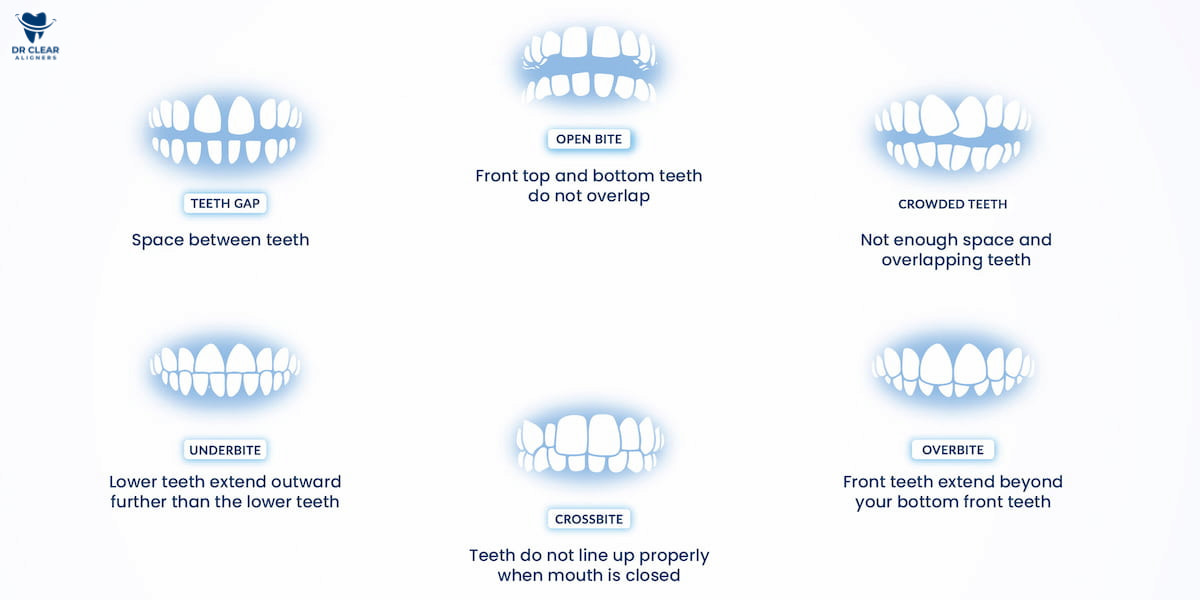

There are 6 different types of malocclusions:

1. Overbite

2. Underbite

3. Open bite

4. Overcrowded

5. Crossbite

6. Gap Teeth

An overbite is a common form of malocclusion where the upper teeth extend over the lower teeth. If your teeth follow a similar pattern, you may be dealing with an overbite. Let’s explore the causes of overbite to help you better understand this type of teeth misalignment.

An underbite is a type of dental malocclusion where the lower teeth extend beyond the upper teeth. This condition can lead to various issues, such as difficulty chewing and an increased risk of developing conditions like sleep apnea.

An open bite refers to a type of teeth misalignment where the upper and lower teeth do not touch when the mouth is closed. In severe cases, this condition may require surgical intervention to correct the jaw alignment.

Crowded teeth, also known as crooked teeth, occur when there isn’t enough room in the mouth for the teeth to align properly. As a result, the teeth may shift, overlap, and crowd together.

A crossbite is a type of teeth misalignment where the upper teeth do not align properly with the lower teeth when the mouth is closed. It occurs when one or more of the lower teeth extend past the upper teeth.

Gap teeth, also known as diastema, are characterised by a visible space between two teeth. This gap can occur between any teeth but is most commonly seen between the two front teeth.